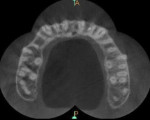

A 25-year-old male patient reported to the outpatient department with the chief complaint of pain in the left upper back region of jaw for the last 2 to 3 days. The patient also gave a history of disturbed sleep. Findings from the clinical examination revealed a deep carious lesion in the maxillary left first molar. The tooth was sensitive to percussion and elicited positive response on thermal and electric pulp testing; pain persisted even after removal of the stimulus. An intraoral periapical radiograph revealed a radiolucency approximating the pulp and periodontal ligament space widening was also present (Figure 1). On correlating the clinical and radiographic findings, a diagnosis of acute irreversible pulpitis with apical periodontitis was made and a decision to perform root canal treatment of maxillary left first molar was determined. The patient was informed about the treatment, and he provided informed consent. The patient was administered local anesthesia of 2% lidocaine containing 1:80,000 epinephrine and an access opening was performed using a rubber dam isolation. The clinical evaluation of the internal anatomy revealed 3 principal root canal systems: mesiobuccal (MB), distobuccal (DB), and palatal (P). After careful probing using a DG 16 endodontic explorer (Dentsply Sirona, dentsply.com), under 2.5X magnification using surgical loupes (Keeler Instruments, keelerusa.com), a small hemorrhagic point was noticed in a groove from the MB orifice in a palatal direction. A similar hemorrhagic point was also observed near the orifice of the main palatal canal. The conventional triangular access was modified to a trapezoidal shape to improve access to the additional canals. In both areas, there was a “catch” present with the endodontic explorer. Multiple radiographs at different angulations were not conclusive, so a multislice CBCT (Kodak, Carestream, carestreamdental.com) scan was performed of the involved tooth along with adjacent teeth. All required measures were taken to protect the patient from radiation. The images were obtained in transverse, axial, and sagittal sections of 0.5-mm thickness, which is used routinely. CBCT scan slices revealed 5 canals (2 mesiobuccal, 2 palatal, and 1 distobuccal) in the axial images at the coronal (Figure 2) and middle thirds (Figure 3). In the apical third, the palatal root had only 1 canal indicating that the 2 canals were fused between middle and apical thirds (Figure 4).